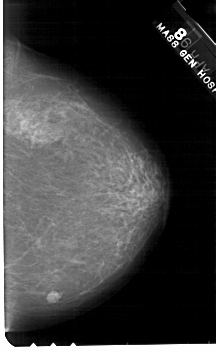

A_1562_1.LEFT_MLO

LEFT_MLO LINES 5491 PIXELS_PER_LINE 3541 BITS_PER_PIXEL 12 RESOLUTION 43.5 OVERLAY